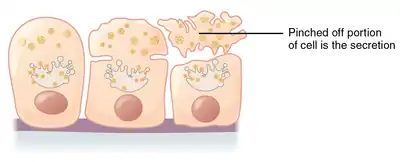

| Apocrine – by membrane budding (loss of cytoplasm) |

Apocrine (/ˈæpəkrɪn/)[1] is a term used to classify the mode of secretion of exocrine glands. In apocrine secretion, secretory cells accumulate material at their apical ends, and this material then buds off from the cells, forming extracellular vesicles. The secretory cells therefore lose part of their cytoplasm in the process of secretion.

Apocrine secretion is less damaging to the gland than holocrine secretion (which destroys a cell) but more damaging than merocrine secretion (exocytosis).